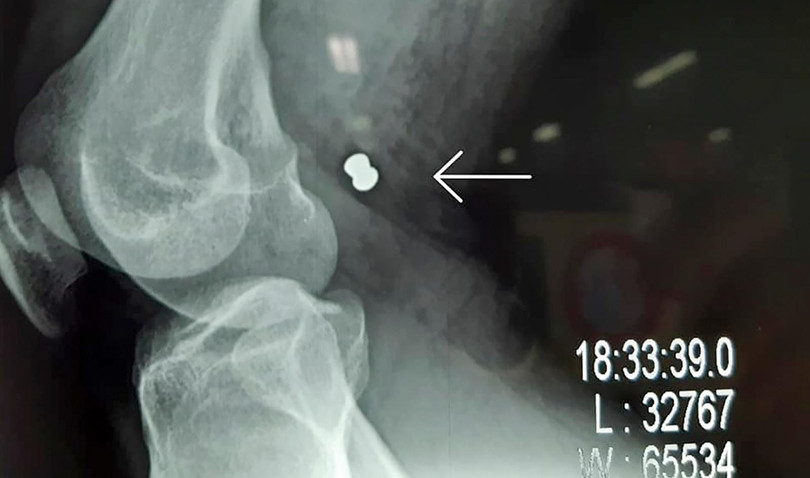

Phim X-ray chụp viên đạn ghim vào đùi gây vở động mạch và tĩnh mạch đùi của bạn nhân

Sau khi siêu âm, chụp X-quang, bác sĩ xác định trong đùi phải anh H. có viên đạn, khả năng làm tổn thương các mạch máu nên phải phẫu thuật khẩn cấp.